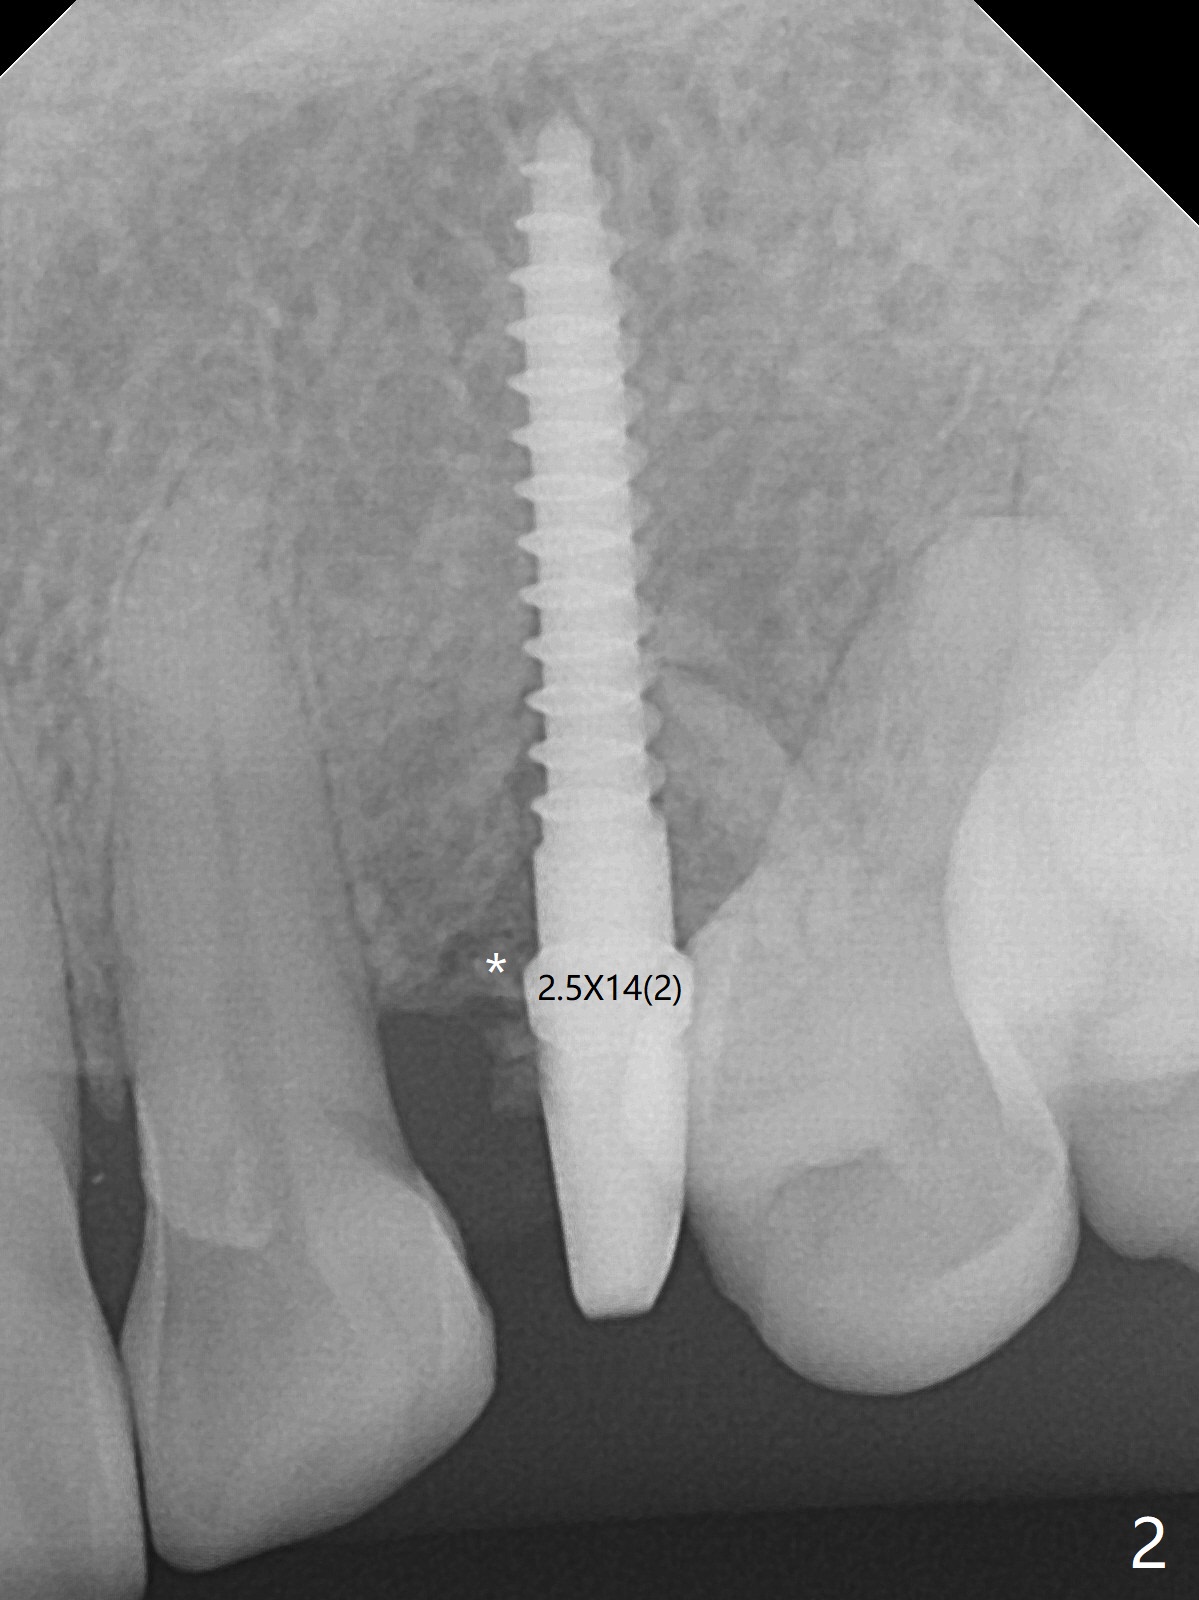

At surgery, the mesiodistal space for #11 is found to be narrow, 5 mm. To prevent buccal plate collapse, socket shield is planned. Due to limited space, incision is attempted so that the lower end of the shield (Fig.1 S) can be trimmed slightly subcrestal. It is also good for visibility for osteotomy (1.2 mm drill for 12 mm). A 2.5x14(2) mm 1-piece implant is placed with <35 Ncm (Fig.2,3 (*: allograft)). An immediate provisional is fabricated to the patient's satisfaction. There is no bone loss 3.5 months postop (Fig.4) or 4 months postop (Fig.5 *, corresponding to S in Fig.3). The recessive papillae are expected to reform to certain degree due to limited damage to the crestal bone.